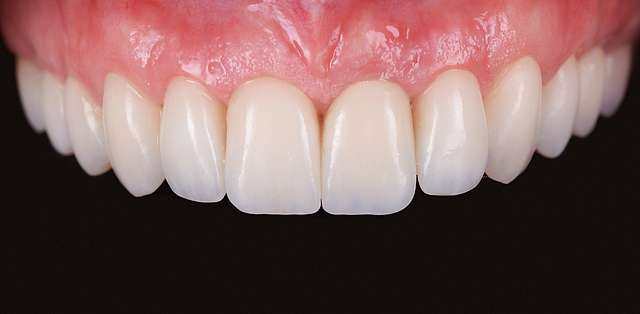

Using tissue grafts to correct gingival levels or cover recessions

Using tissue grafts to correct dark color of gingiva